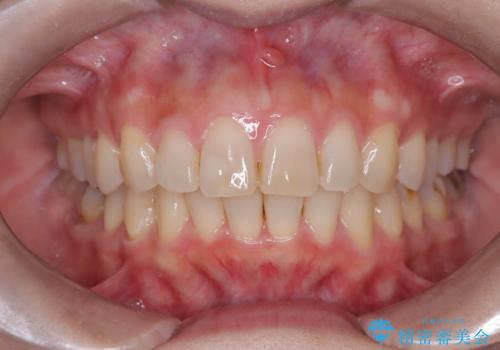

- 口元が出ていることを主訴に来院されました。

歯を抜いてスペースを作ることで、前歯を下げることができました。

ハーフリンガルということで治療期間が3年近くかかりましたが、口元もしっかり下がり満足していただきました。